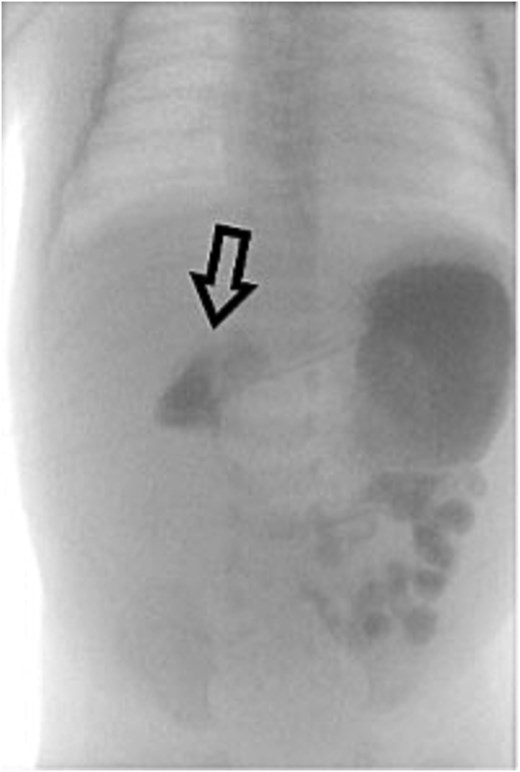

However, she returned the next day with recurrent bilious vomiting. Abdominal X-ray demonstrated a paucity of bowel gas and a fluid-filled stomach. Repeat UGI series showed delayed transit from the second to fourth portions of the duodenum, suggesting a partial obstruction (Fig. 3). Exploratory laparotomy revealed recurrent midgut volvulus with two full twists at the duodenojejunal junction. The volvulus was successfully reduced, small adhesions lysed, and no bowel resection was required. The infant recovered uneventfully in the pediatric intensive care unit and was discharged on postoperative Day 8. She has been seen in outpatient clinic and is progressing well.

Repeat UGI series reveals delayed transit from the second to fourth portions of the duodenum, suggestive of partial obstruction likely due to adhesions.